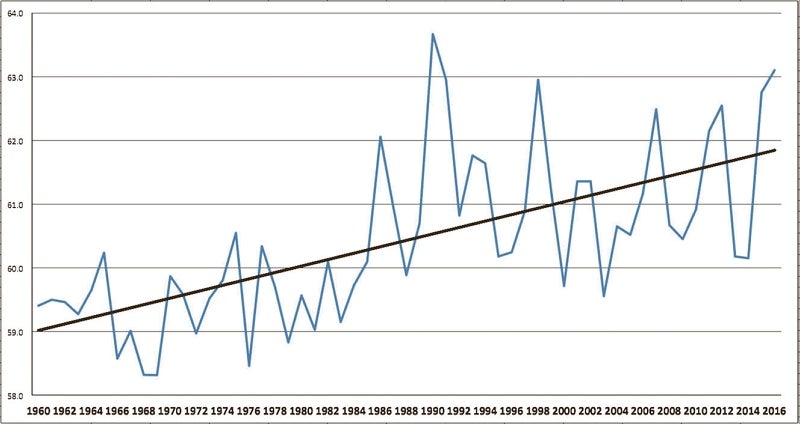

By Francis Koster Special to the Salisbury Post Pop Quiz: What does this graph show? A. The growth in debt of the State of North ...

Since the passage of the Clean Air Act in 1970, America has become much healthier. According to the New England Journal of Medicine, our average ...